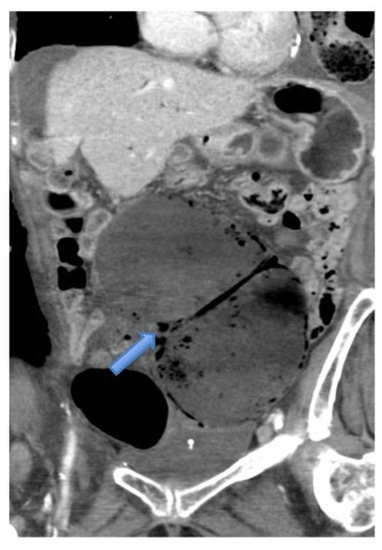

4.4.2. Computerised Tomography (CT) Scan

- CT scan confirms diagnosis in >90%

- Typical Radiological Signs are described

- Representative X-ray and CT images presented

| CT Abdomen and pelvis | 15 | One patient operated without CT. |

| CV not described | 1 | |

| CV correctly identified | 14 (93.3%) | |

| Caecal diameter >10 cm | 10 (67%) | |

| Whirl sign | 12 (80%) | |

| Split-wall sign | 13 (86.6%) | |

| X-marks-the-spot sign | 14 (93.3%) | |

| Double transition point | 13 (86.6%) | |

| Ileocaecal twist | 13 (86.6%) | |

| Central appendix | 11 (73.3%) |